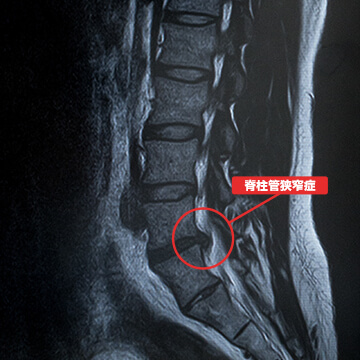

- 腰部脊柱管狭窄症

腰部脊柱管狭窄症とは脊柱管と呼ばれる神経の通り道が狭くなる病気のことを言います。椎間板ヘルニアと同様に腰痛や坐骨神経痛の症状に加え、間欠性跛行(かんけつせいはこう)と呼ばれる症状が現れます。脊柱管狭窄症は体を反らすと痛みが出て、体を丸めると症状が緩和するといった特徴があります。